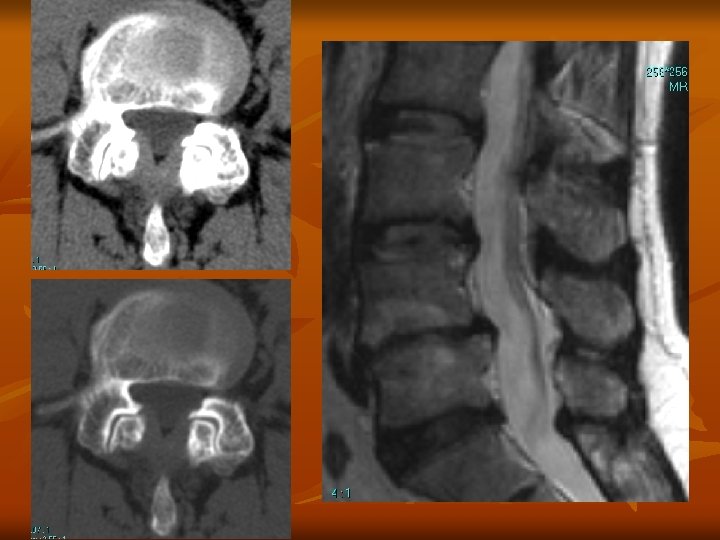

Hernia (porckorongsérv) n n A belső mag (nucleus pulposus) a fibrózus külső gyűrűn keresztül (annulus fibrosus) előboltosul. Az annulus fibrosus szakadása a hernia helyén fájdalmat okoz Hernia tipusok: n n n n Szétterült korong Discus protrusio Prolapsus Szekveszter (kiszakadt sérv) Éles, metsző fájdalom Izomerő és érzészavar a neurológiai vizsgálat során, reflexeltérések MR CT

Hernia fokozatok